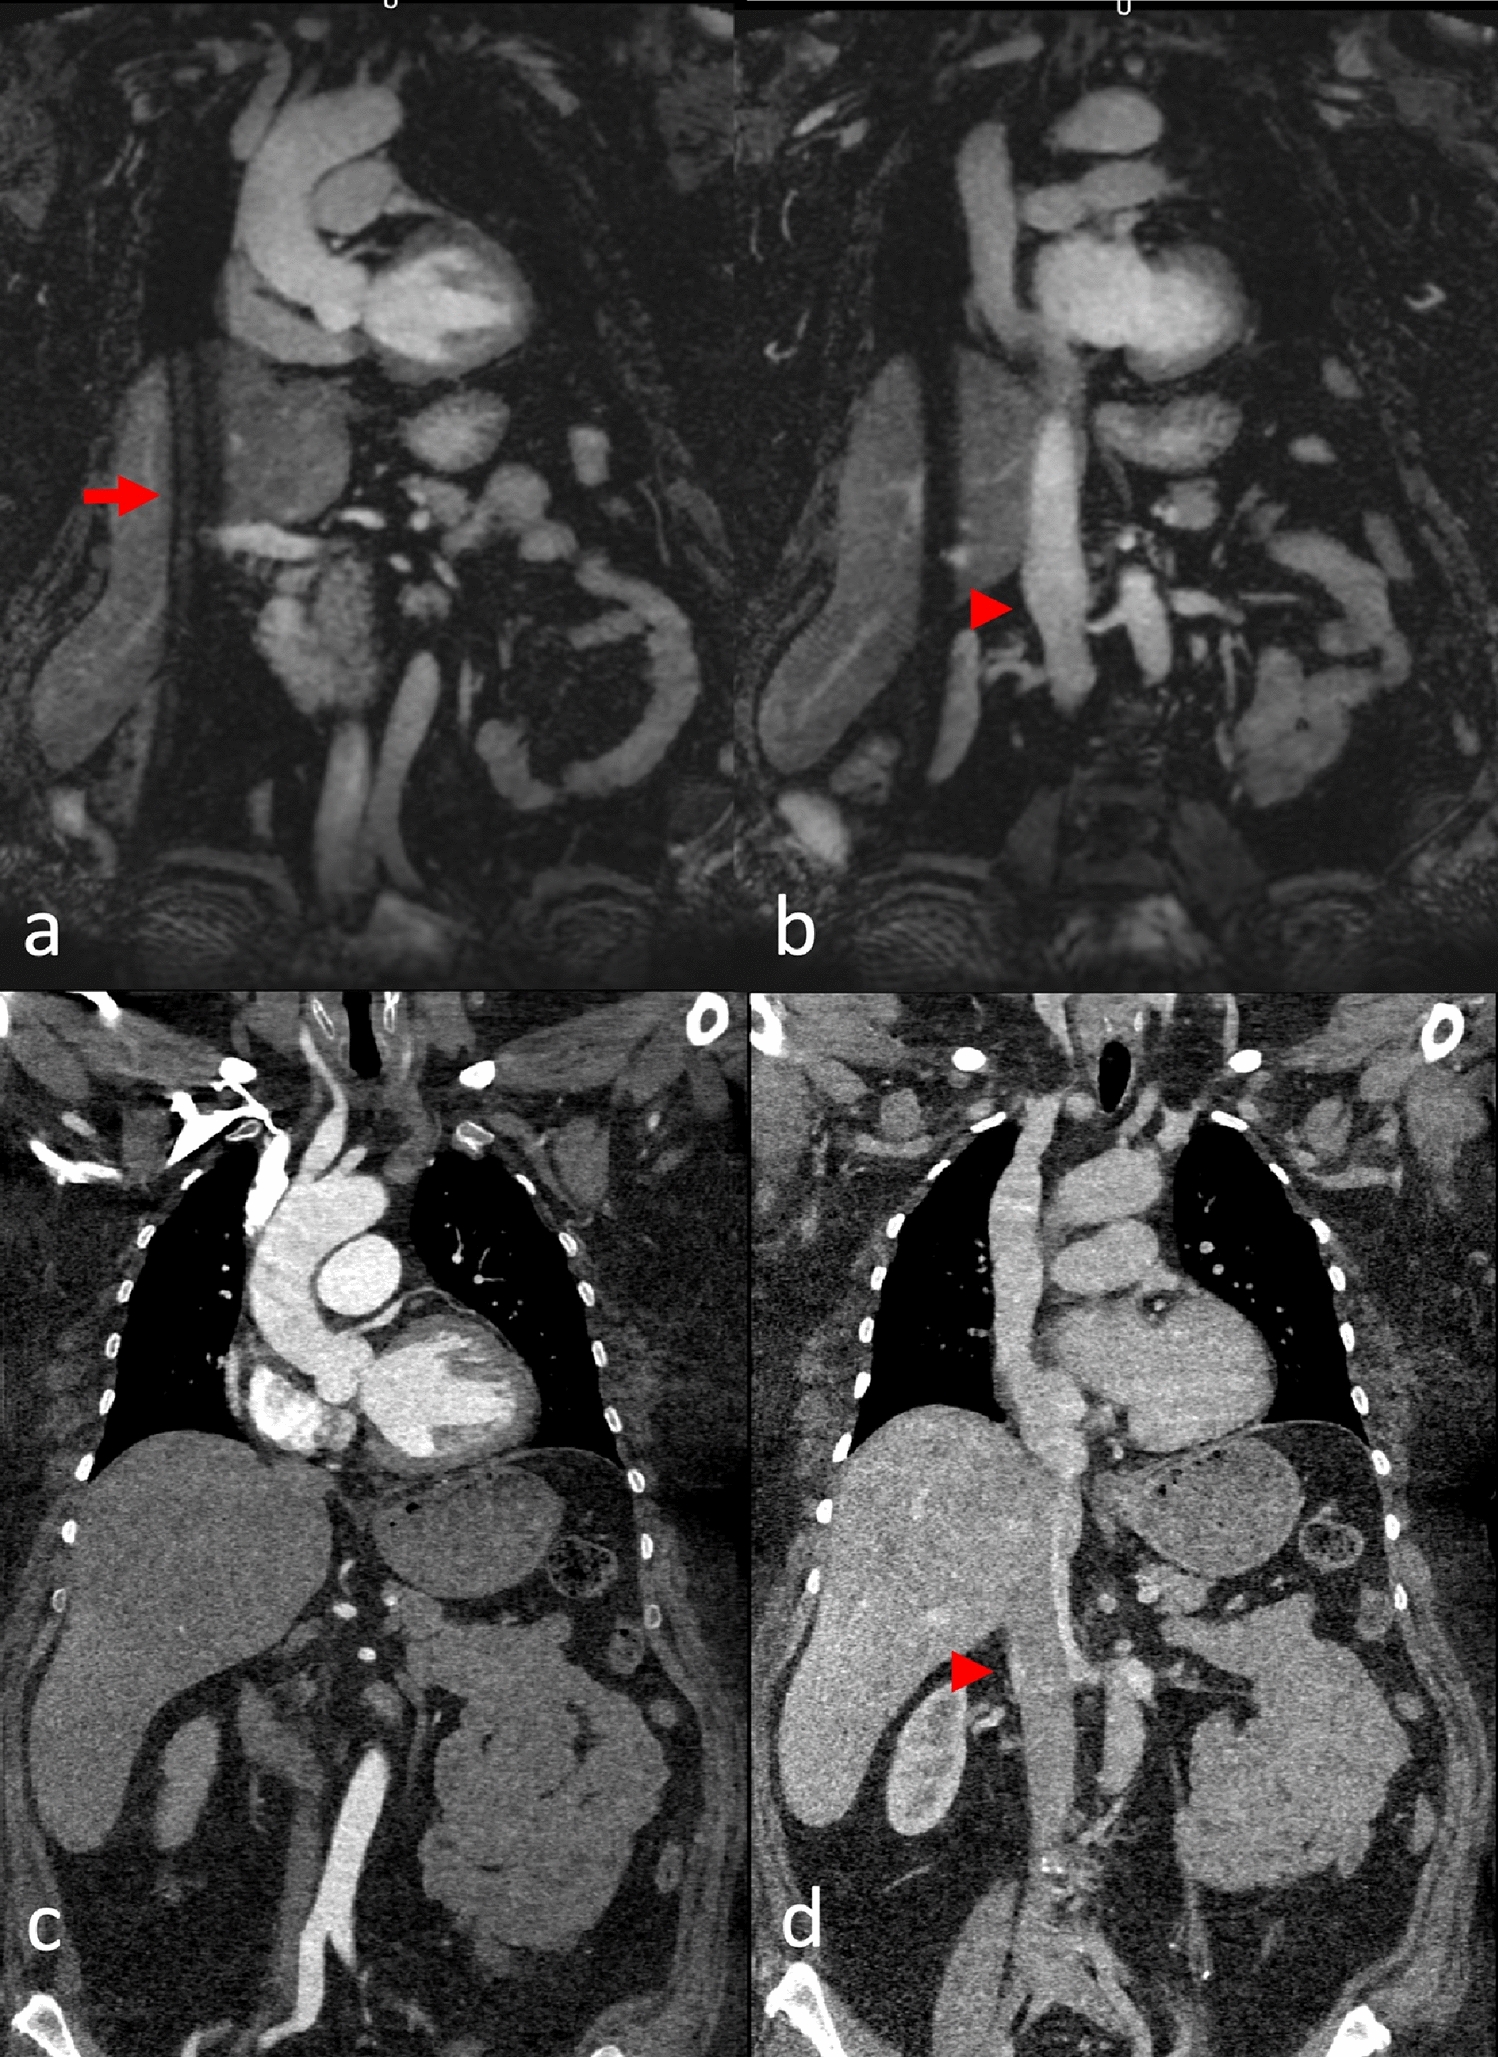

Fig. 2

This patient was admitted to the Emergency Department for acute thoracic pain and a difference in pulse between arms. The initial CT scan ruled out aortic dissection. Native coronal MRA images (a, b) and corresponding CTA reformations (c, d) at the level of the ascending aorta (a, c) and venae cavae (b, d). A typical MRA navigator artifact is seen over the right hemibody (arrow). There was insufficient contrast in the IVC in the CTA due to an influx of contrasted blood from the renal veins but excellent contrast in the MRA (arrowheads)